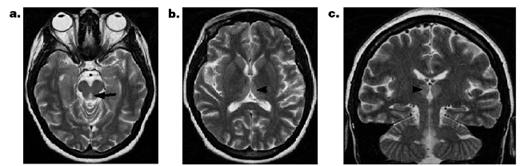

男,26歲,肥胖行減肥手術,術后頑固性嘔吐。臨床表現(xiàn)為淡漠、共濟失調、眼肌麻痹。T2WI示導水管周圍、丘腦背內側高信號。胼胝體壓部彌散受限、ADC減低。

患者表現(xiàn)為意識障礙、肢體不自主運動、小腦性共濟失調、眼球震顫、雙側外直肌麻痹。顱腦MRI示:雙側小腦齒狀核(空箭頭)、前庭神經(jīng)核(白色箭頭)、展神經(jīng)核異常信號(短箭頭);中腦頂蓋、雙側黑質及乳頭體對稱性異常信號。